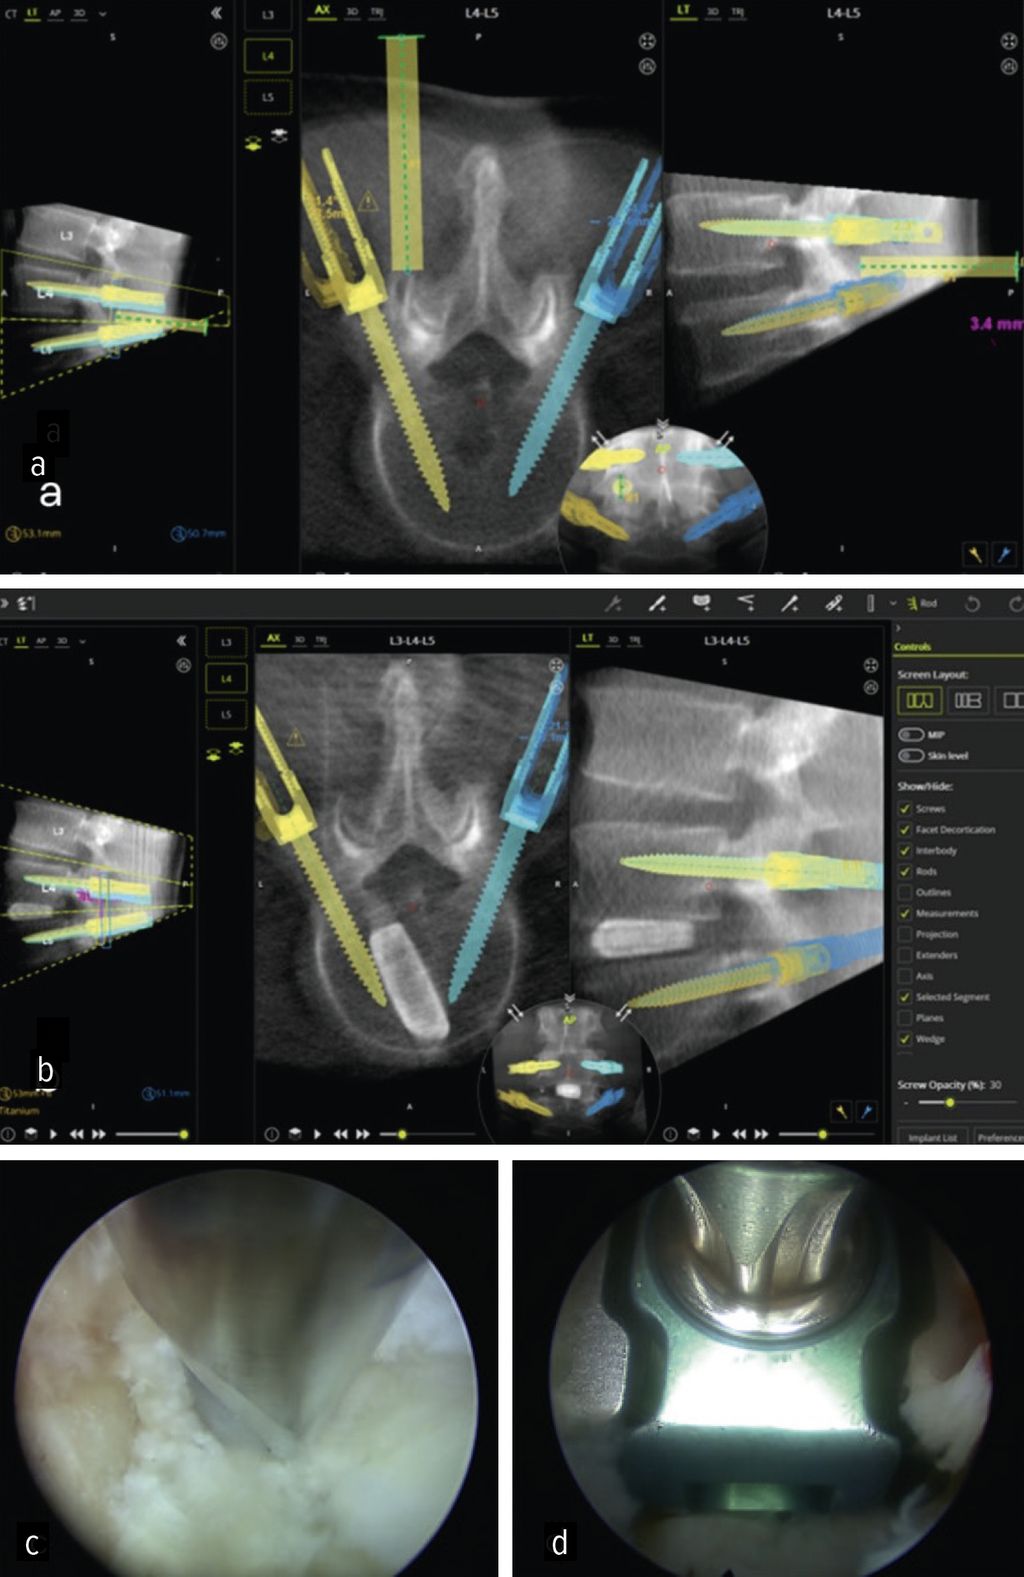

Die minimalinvasive transforaminale lumbale interkorporelle Fusion (Minimally Invasive Transforaminal Lumbar Interbody Fusion; MIS-TLIF) hat in den letzten Jahren an Bedeutung gewonnen, die aufgrund des geringeren Gewebetraumas mit einer früheren Rekonvaleszenz verbunden ist.24 Aus den gleichen Gründen rückt die endoskopische transforaminäre InterbodyFusion (Endo-TLIF) in den Fokus der Aufmerksamkeit. Endo-TLIF ist eine Erweiterung der MIS-TLIF und erfordert eine unilaterale Resektion des Facettengelenkes. Die Grund- und Deckplattenpräparation gilt als entscheidender Faktor, der die Fusionsrate beeinflusst.24 Die Möglichkeit, unter klarer endoskopischer Sicht die Endplatten präzise darzustellen, erlaubt eine ideale Aufbereitung des Fusionsbettes. Dies könnte zu einer Erhöhung der Fusionsrate beitragen. Zudem profitieren die Patienten durch eine raschere Erholung, einen geringeren Opioidbedarf, eine frühzeitige Mobilisierung und eine verkürzte stationäre Verweildauer.25 Limitationen liegen aktuell bei höhergradigen Listhesen und kollabierten Bandscheibenräumen vor.26 Um das Potenzial der Methodik zu untermauern, bedarf es robuster Studien mit erhöhtem Evidenzlevel sowie eines einheitlichen Standards der endoskopischen Fusionstechniken. Abbildung 6 zeigt eine Planungsanwendung (MazorX® Application, Fa. Medtronic) für Endoskoptrajektorie und Pedikelschraubenimplantation im Rahmen der Endo-TLIF-Operation (a, b). Abbildung b zeigt einen oblique eingebrachten Cage (eFuse® expandable, Fa. Evospine), Abbildung c einen Nukleusresektor (Fa. RIWOspine) bei Präparation des Fusionsbettes. Abbildung d zeigt, dass eine Cagedistraktion unter direkter Sicht möglich ist.